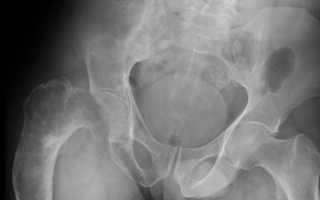

- Гинекологический осмотр. Бимануальное исследование позволяет выявить округлое эластическое образование в проекции придатков. В большинстве случаев опухоль односторонняя, поверхность ее может быть гладкой или бугристой.

- Ультразвуковое исследование. При УЗИ текома определяется как округлое гипоэхогенное образование с четкими контурами. Внутренняя структура обычно однородная, без очаговых включений. При допплерометрии кровоток внутри доброкачественной опухоли отсутствует.